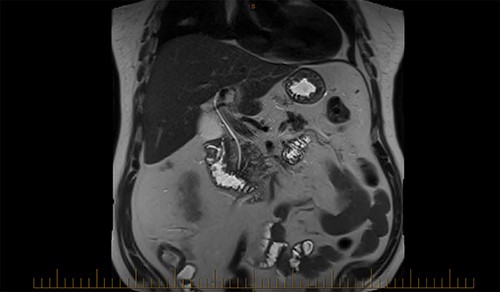

The acute surgical unit consulted upon the patient and a CT abdomen with oral contrast was performed the next day. CT was unable to accurately identify the position and nature of the foreign object. Filling defects with the stomach fundus and superior part of duodenum were identified, but the FB remained unidentified.

A magnetic cholangiopancreatography (MRCP) was performed to exclude a cholecystoduodenal fistula. A filling defect within the duodenum was identified on the scan; however, there was no evidence of a fistula (Fig. 6).

On Day 7, a repeat upper gastrointestinal endoscopy was performed. The FB remained in the first part of the duodenum which it had begun to erode through posteriorly (Fig. 7). The endoscopy was fitted with an overtube and with the help of a snare the embedded FB was successfully retrieved.